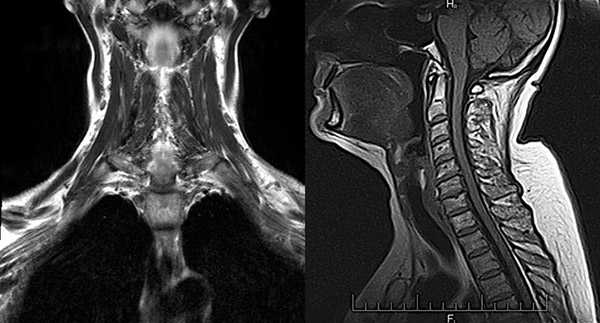

МРТ слюнных желез что показывает

МРТ слюнных желез — неинвазивный метод визуализации мягких тканей ротовой полости, в частности органов, вырабатывающих слюну. Позволяет оценить характер работы желез, степень сохранности секреторной активности, присутствие инородных тел и опухолей. В деле раннего выявления патологий указанного участка МРТ слюнных желез находится вне конкуренции: это единственная безопасная методика, обладающая достаточной информативностью.

МРТ слюнных желез с контрастом

МРТ с контрастом дает возможность на ранних стадиях выявить опухолевые образования в структуре слюнных желез, определить их размеры, локализацию, форму, строение, степень васкуляризации (кровоснабжения). Это требуется, в том числе, перед проведением хирургического лечения для определения объемов вмешательства и стратегии терапии, биопсией. На основании данных МРТ с контрастом можно сделать предварительный вывод о злокачественности или доброкачественности новообразования.

- Сейчас по информативности на первом месте стоит МРТ, за ним следует КТ. Магнитно-резонансная томография является безопасной, неинвазивной и наиболее информативной методикой обследования. Позволяет оценить размеры и форму, структуру железы, детализировать информацию о протоках, рассмотреть соседние анатомические структуры.